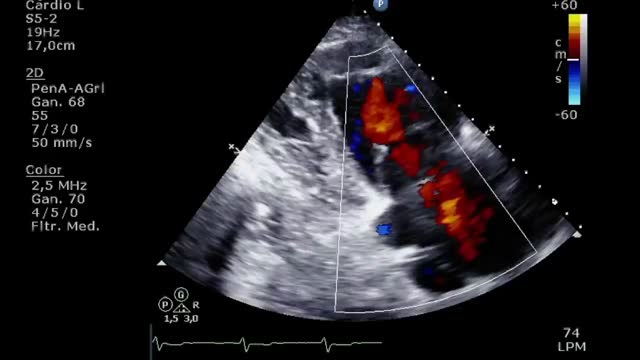

A 74-years-old man with a history of ascendant aortic dissection repaired 5 years ago and two mayor episodes of intrathoracic infection needing long-term antibiotic treatment, came to the ER for a presternal tumor. CT scan detected a preaortic mass suggestive of an aortic pseudoaneurysm. Surgery was planned but cancelled for mild respiratory infection, acute renal and hepatic failure, needing ICU admittance. In the ICU, the patient at physical exploration neck engorgement and pulsatility stood up (video 1). Vascular and cardiac bedside ultrasound showed a reversed systolic flow in the jugular veins (video 2) and a severe triscuspid regurgitation (video 3) secondary to pulmonary hypertension due to extrinsic compression of the psedoaneurysm over the pulmonary artery (white arrow in Fig. 1). The patient rejected aggressive treatment and passed away 2 days later.